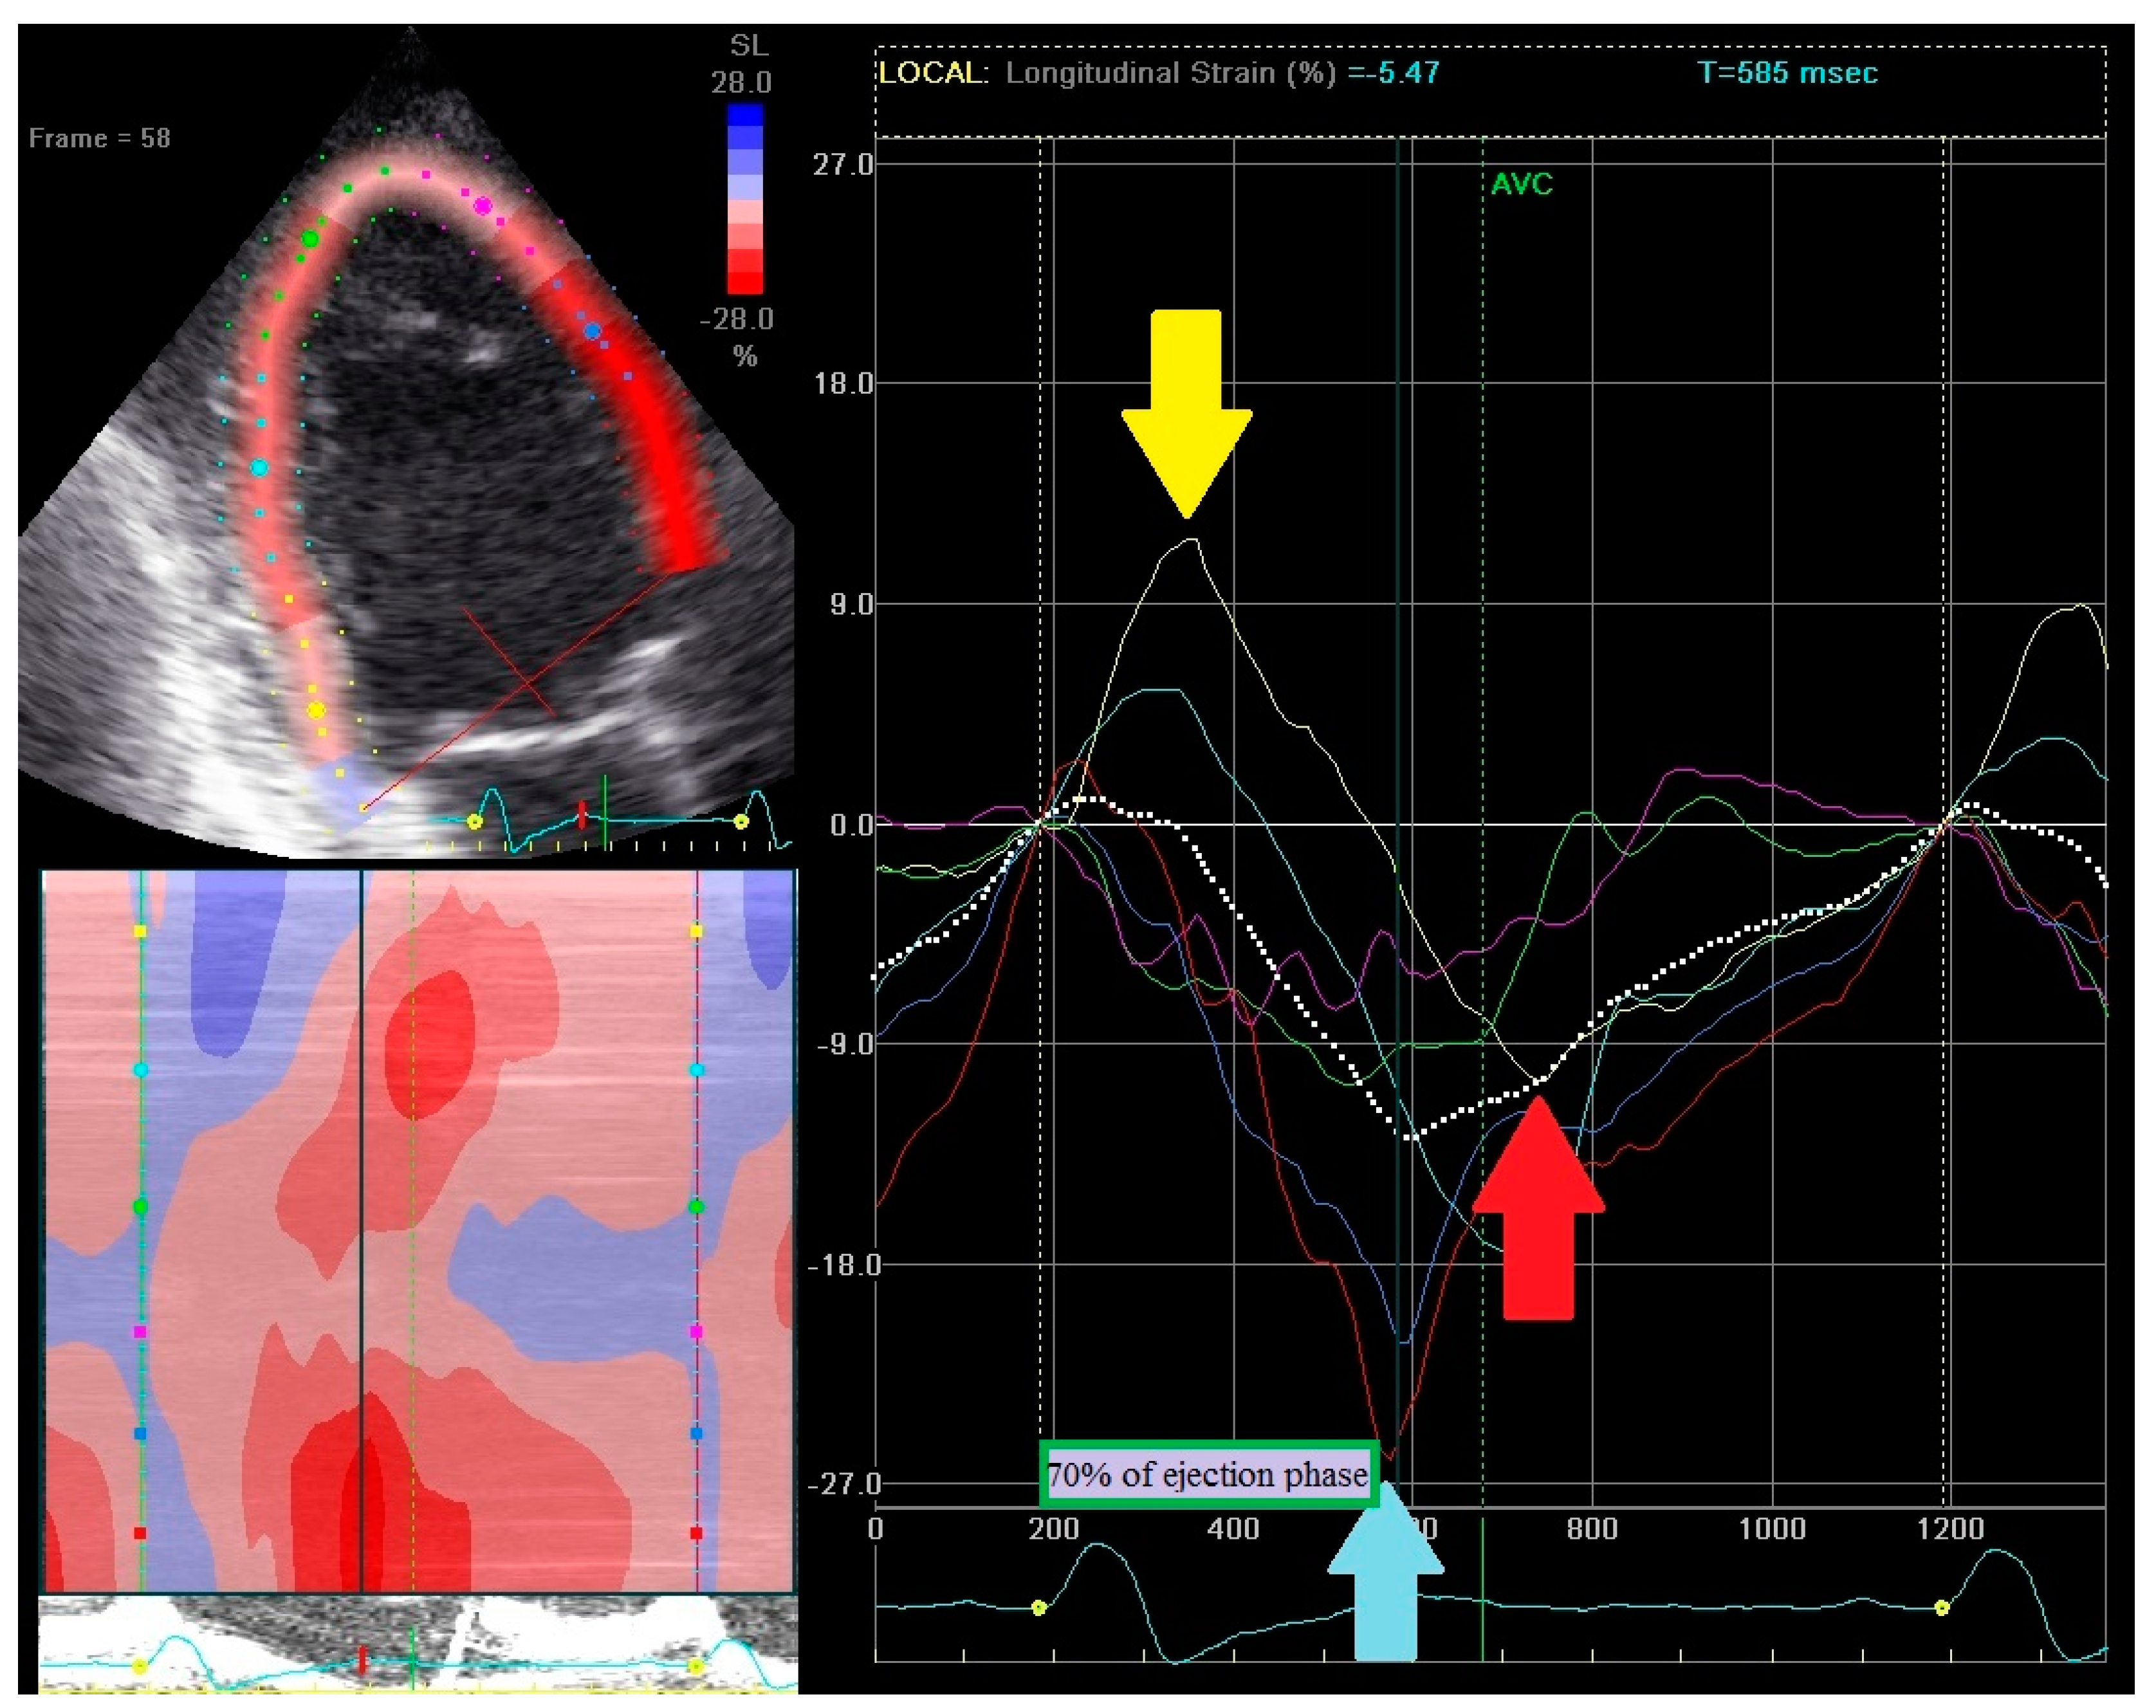

- (1)

- Early contraction of at least one basal or midventricular segment in septal or anteroseptal wall and early stretching in at least one basal or midventricular segment in the opposing wall,

- (2)

- the early peak contraction does not exceed 70% of the ejection phase,

- (3)

- the early stretching wall shows a peak contraction after aortic valve closure.